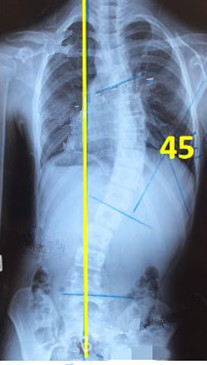

脊柱側(cè)彎矯形器(支具)是通過外力對側(cè)彎的脊柱進(jìn)行矯正。所以,支具的力點位置及大小非常重要。當(dāng)患者生長發(fā)育速度較快或支具矯正效果較好時,側(cè)彎矯正的進(jìn)程也會較快,此時為了充分利用孩子生長階段的最佳矯正期,一定要對支具進(jìn)行及時的調(diào)整和更換。

一般經(jīng)過三個月至六個月的治療,對稱度都能得到改善,力線回正。

此時由于患者已經(jīng)完全適應(yīng)支具的力點,且體表變化較大,為了進(jìn)一步矯正,我們需要對支具進(jìn)行調(diào)整。如果由于孩子身高的變化較大,為了更進(jìn)一步的矯正,可以考慮更換新的支具。

穿支具后